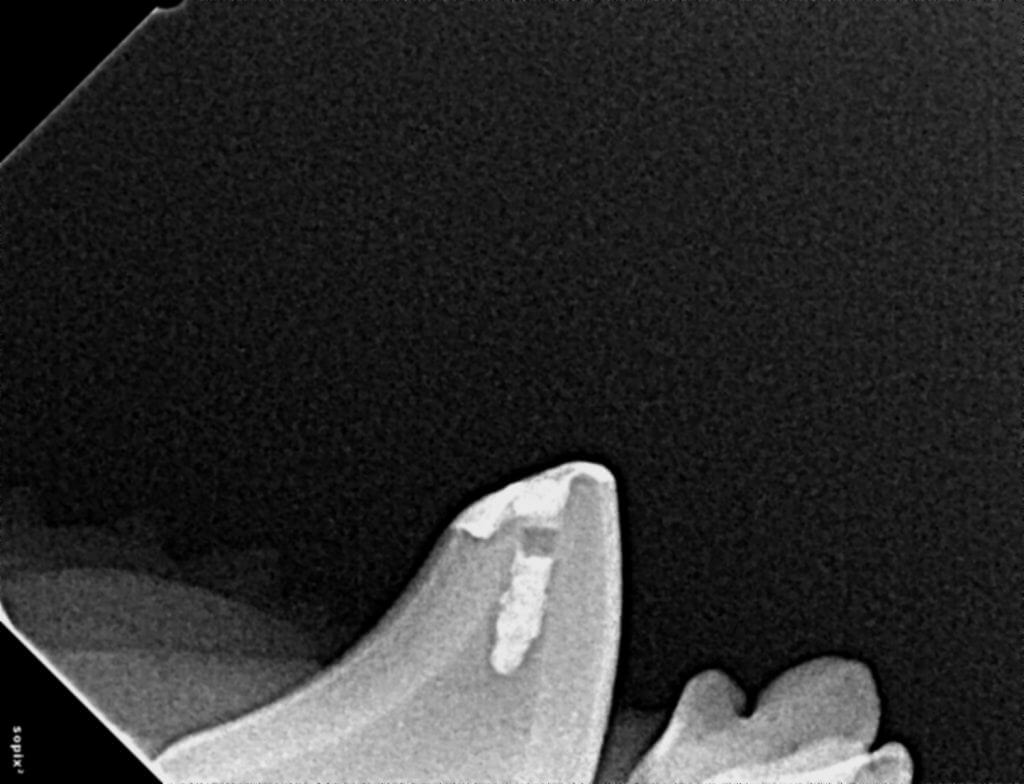

Dr. Hall begins with a thorough oral exam and dental radiographs to assess the tooth's condition. Our team uses digital X-rays and CBCT scans for detailed imaging, allowing us to identify hidden damage or infection beneath the surface.

If a root canal or pulp therapy is needed, our team removes diseased tissue from inside the tooth. The root canal is thoroughly cleaned, disinfected, and filled with a material that seals out bacteria. This technique lets your pet keep their natural tooth and resolve pain.

After the tooth is filled, we restore its function with a protective crown or composite restoration. The healing process is monitored through follow-up appointments, ensuring long-term results and excellent oral health for your pet.